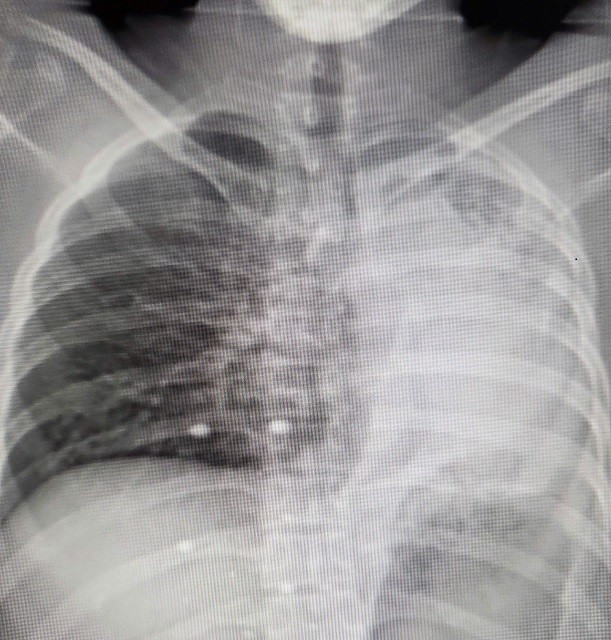

| Hình ảnh phim chụp hẹp phế quản gốc trái, xẹp hoàn toàn phổi trái do di chứng của lao phổi - Ảnh BVCC |

Anh B được chuyển đến Khoa Phẫu thuật Lồng ngực, Bệnh viện Bạch Mai. Qua các thăm khám lâm sàng và chụp chiếu, kết quả quả cho thấy, anh B đối diện với nguy cơ mất phổi vĩnh viễn: Chụp CT 3D phổi cho thấy phế quản gốc trái chỉ còn khe hẹp 2mm, phổi xẹp đặc như tấm bìa cứng. Nếu không phẫu thuật trong 2 tuần, phổi sẽ hoại tử.